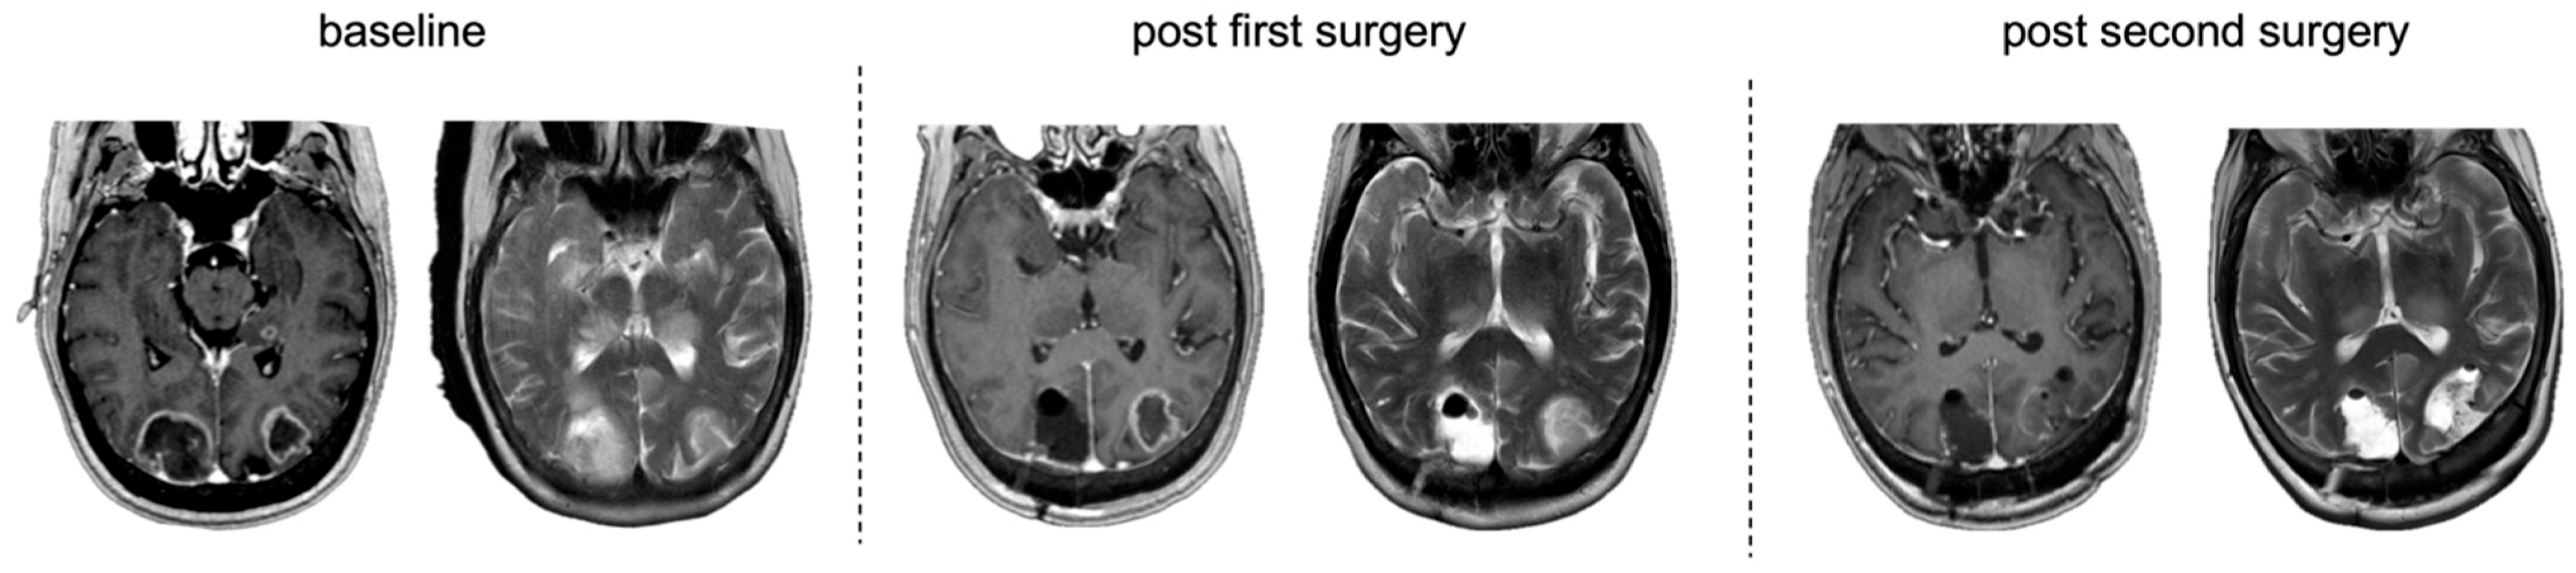

3.5.2. Non-Compliance at the First Surgery